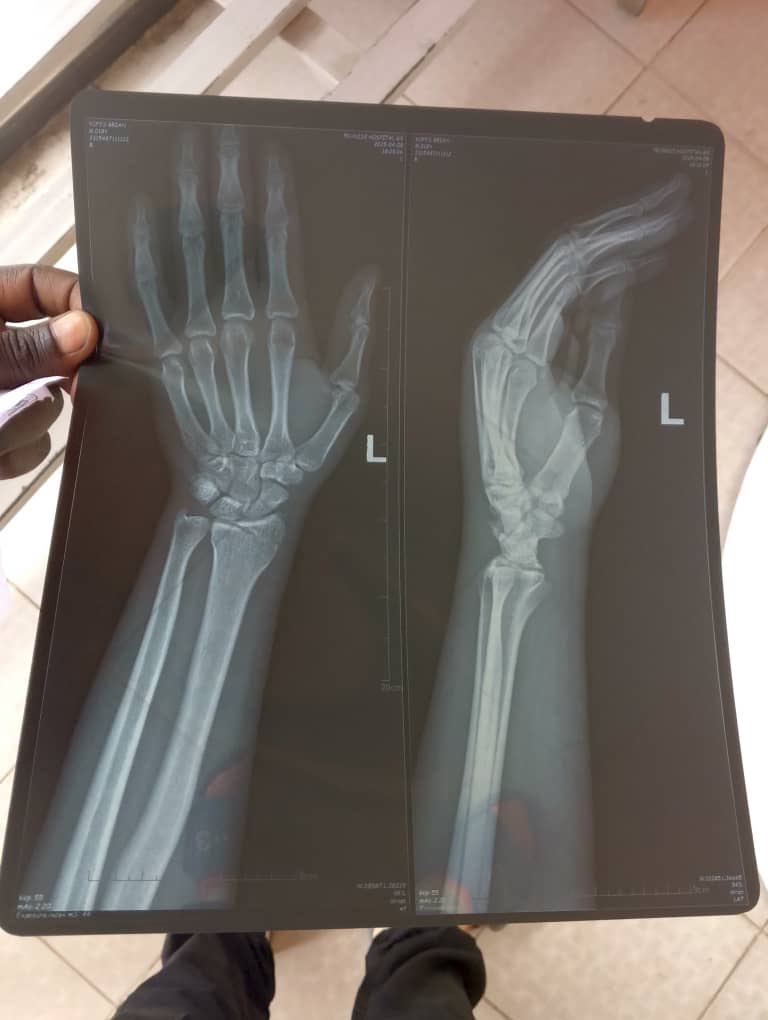

The refugee camp was attacked under the night. The camp is located in a very homophobic region and are attacked often. Members of the camp have been injured and need medical care. They need money for two medical procedures which will cost $1800